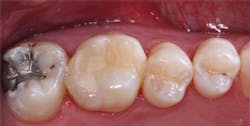

Use of resin-modified glass ionomer as a liner or base

The following technique is for use of RMGI as a liner or base for direct resin-based composite restorations using a self-etch bonding agent. Use of total-etch or selective-etch would be slightly different. Any of the three techniques works well if accomplished properly.

- Place resin-modified glass ionomer on the deepest areas of the tooth preparation, not on the margins. The material should be about 0.5 mm thick or slightly thicker. Cure it.